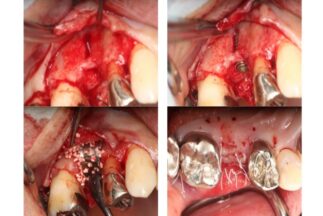

| 治療内容 | 上顎右側5相当部へインプラント埋入と同時にチタンメッシュを用いて自家骨と骨補填材による骨増生術を行った |

| リスクについて | 術後感染症 |